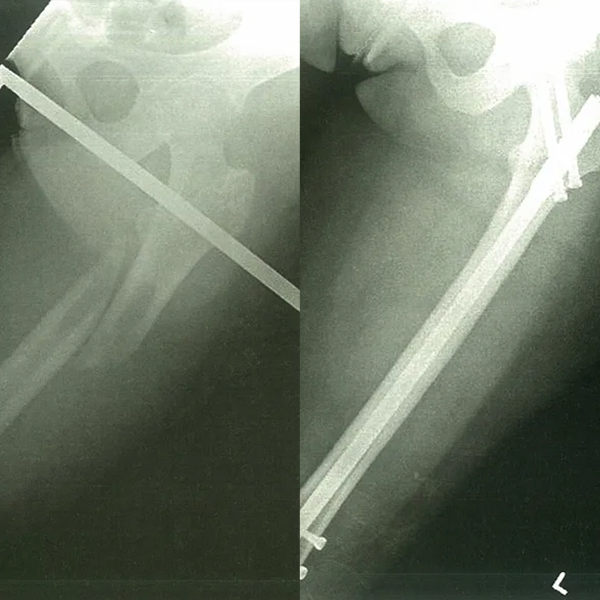

Интрамедуллярная система ногтей - это внутреннее фиксационное устройство, используемое для лечения переломов длинных костей (например, бедренная кость, большеберцовая кость, плечевая кость). Его конструкция включает в себя вставку главного гвоздя в медуллярный канал и закрепление его фиксирующими винтами для стабилизации перелома. Благодаря своему минимально инвазивной природе, высокой стабильности и превосходной биомеханической производительности, он стал ключевым вариантом в современной ортопедической хирургии.

Основной корпус интрамедуллярного гвоздь, обычно изготовленного из титана или нержавеющей стали, вставленного в медуллярный канал, чтобы обеспечить осевую стабильность.

Используется для обеспечения главного ногтя к кости, предотвращая вращение и укорочение. Включает в себя статические фиксирующие винты (жесткая фиксация) и динамические фиксирующие винты (позволяя сжать осевое сжатие).

Case1

Case2